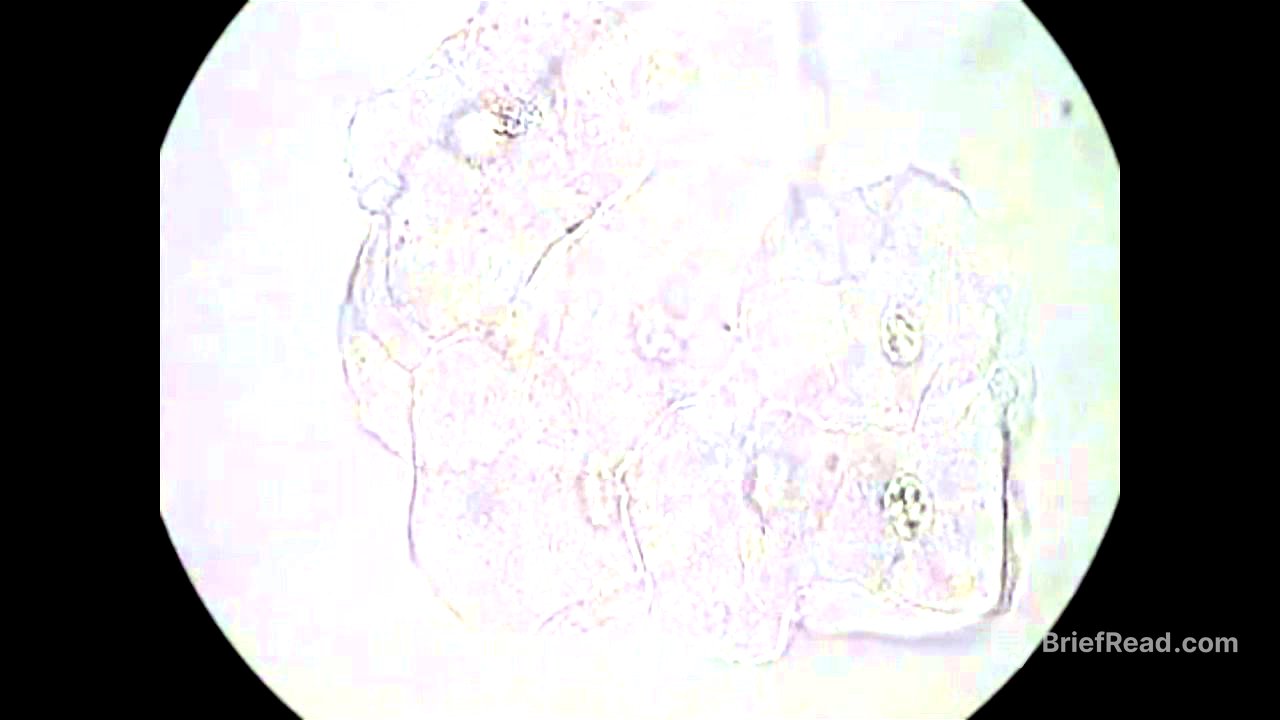

The video describes the key cells and organisms that may be found in vaginal wet mounts. Normal squamous epithelial cells are large, flat cells with a small nucleus. Polymorphonuclear leukocytes (PMNs), or white blood cells, are small, round cells with multiple nucleus lobes, indicating possible infection if found in large numbers. Trichomonads are pear-shaped protozoa identified by their jerking movement via flagella. Clue cells are squamous epithelial cells coated with bacteria, obscuring at least 75% of their borders, and are associated with bacterial vaginosis. Yeast can appear as pseudohyphae (branching, tubular forms) or budding yeast (paired cells resembling a shoe print).

The video demonstrates the examination of various patient samples under the microscope. It shows normal squamous epithelial cells, red blood cells, PMNs, and bacteria (likely lactobacilli). Examples of trichomonads moving in a jerky motion, clue cells with bacteria-covered surfaces, and budding yeast are presented. The video also highlights the importance of distinguishing between true clue cells and epithelial cells with some bacteria, as well as recognising artifacts. Both saline and KOH preps are used to identify pseudohyphae and budding yeast, with the KOH prep providing a clearer view due to lysed background cells.